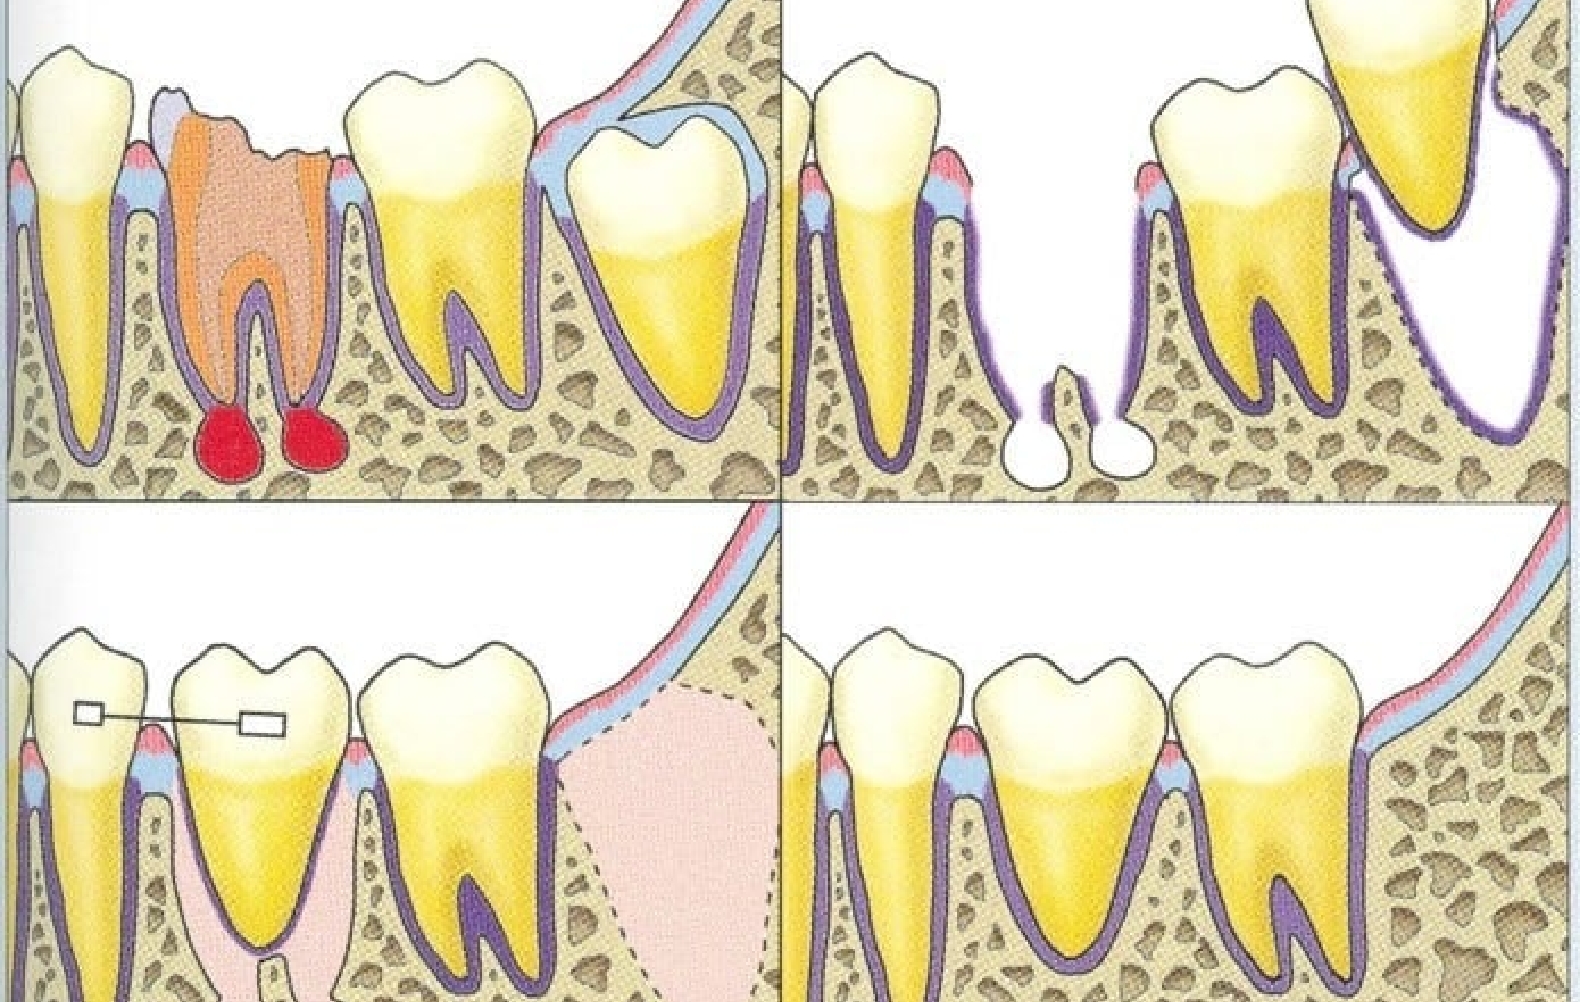

親知らずや埋伏歯など、噛み合わせに関与しない歯を抜歯予定部位へ移す治療です。

歯根膜ごと移植することで骨や歯ぐきと自然に馴染み、咬合圧や食感を繊細に感じ取れる点が最大の特徴です。

歯を抜いたその日に移植する「抜歯即時移植」が最も治癒に有利です。

抜歯窩の側壁に残る歯根膜が活性化し、治癒を促すためです。ただし次のようなケースでは、数週間待ってからの早期移植を選択します。

移植・固定

ドナー歯を受容部に移植し、ワイヤーや糸で固定します。